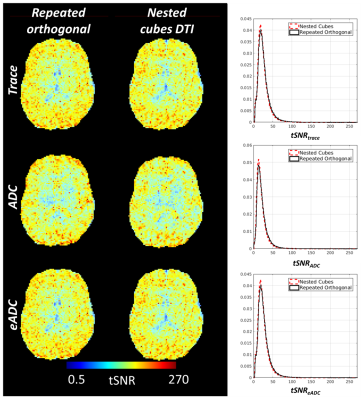

Figure 2. tSNR of trace, ADC and eADC were compared between two dynamic diffusion acquisitions (b = 1000 s/mm2), one with diffusion weighting along three mutually orthogonal directions repeated five times for a total of three unique orientations (left) and the other consisting of diffusion weighting along five sets of three mutually orthogonal directions (nested cubes) for a total of fifteen unique directions (middle). Color bar is on a log scale. Probability distributions of tSNR in gray and white matter voxels for trace, ADC and eADC were similar between the two acquisitions (right).